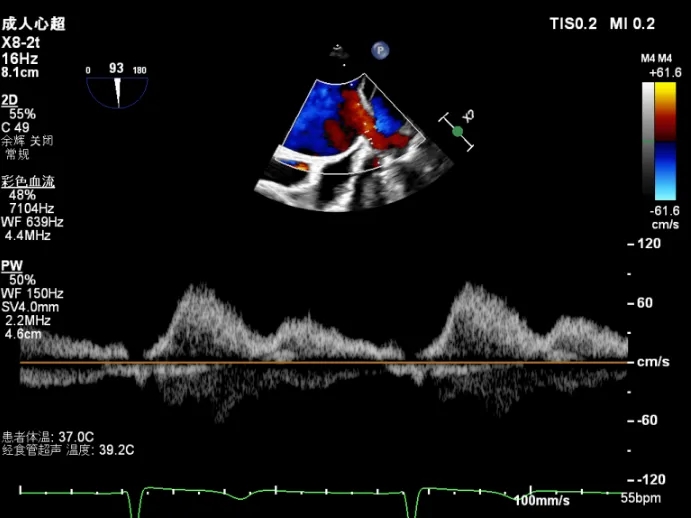

夹子释放后,2D下color,反流降至轻度

夹子释放后3D下观察组织桥稳定,反流降至trace

夹子释放后压差为2mmHg